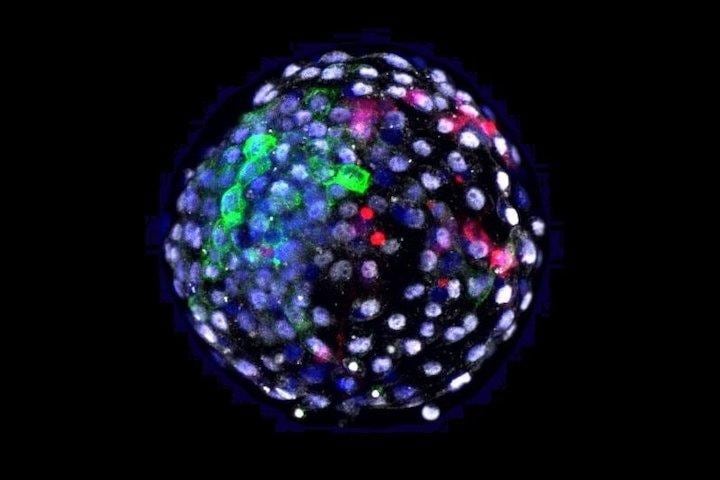

サルの胚にヒトの幹細胞を注入して実験室で人工的に培養された、サルとヒトとの遺伝子型の細胞が混在する「キメラ」の胚が、受精から最長19日間、成長したことが明らかとなった。

サル胚にヒト幹細胞が接着して胚盤が見えるまでに成長

米ソーク研究所と中国・昆明理工大学の共同研究チームは、受精から6日経ったカニクイザルの初期胚盤胞132個にそれぞれヒト多能性幹細胞25個を注入し、経過を観察した。

受精から10日後、そのうちの92.8%にあたる111個のサル胚にヒト幹細胞が接着して胚盤が見えるまでに成長したが、17日後にはその数が12個に減少し、19日後まで生存していたのは3個のキメラ胚のみであった。一連の研究成果は、2021年4月15日、学術雑誌「セル」で発表されている。

さらに研究チームは、キメラ胚のゲノム解析を行い、ヒト胚やサル胚と比較した。その結果、キメラ胚の細胞には特有の遺伝子発現プロファイルがあり、キメラ胚で特異に強化された細胞シグナル伝達経路や、キメラ胚で特に豊富な新たな細胞シグナル伝達経路も確認された。キメラ胚の内部でヒトとサルの細胞間コミュニケーションが起こったためではないかとみられている。

ヒトに近縁な非ヒト霊長類のカニクイザルを用いた今回の実験では、ヒト多能性幹細胞が、受精から19日後まで、サル胚の発達に組み込まれていた。また、キメラ胚の内部でヒトとサルの何らかの細胞間コミュニケーションがあることもわかった。研究チームは、一連の研究成果が「ヒトの細胞がどのように発達し、統合するのか」、「異種の細胞が互いにどのようにコミュニケーションするのか」を解明する手がかりになると期待している。また、ベルモンテ教授は、部分的にサル、部分的にヒトの胚で動物を作ろうとするつもりはなく、そのような種で人間の臓器を育てようとするつもりはない、と強調する。